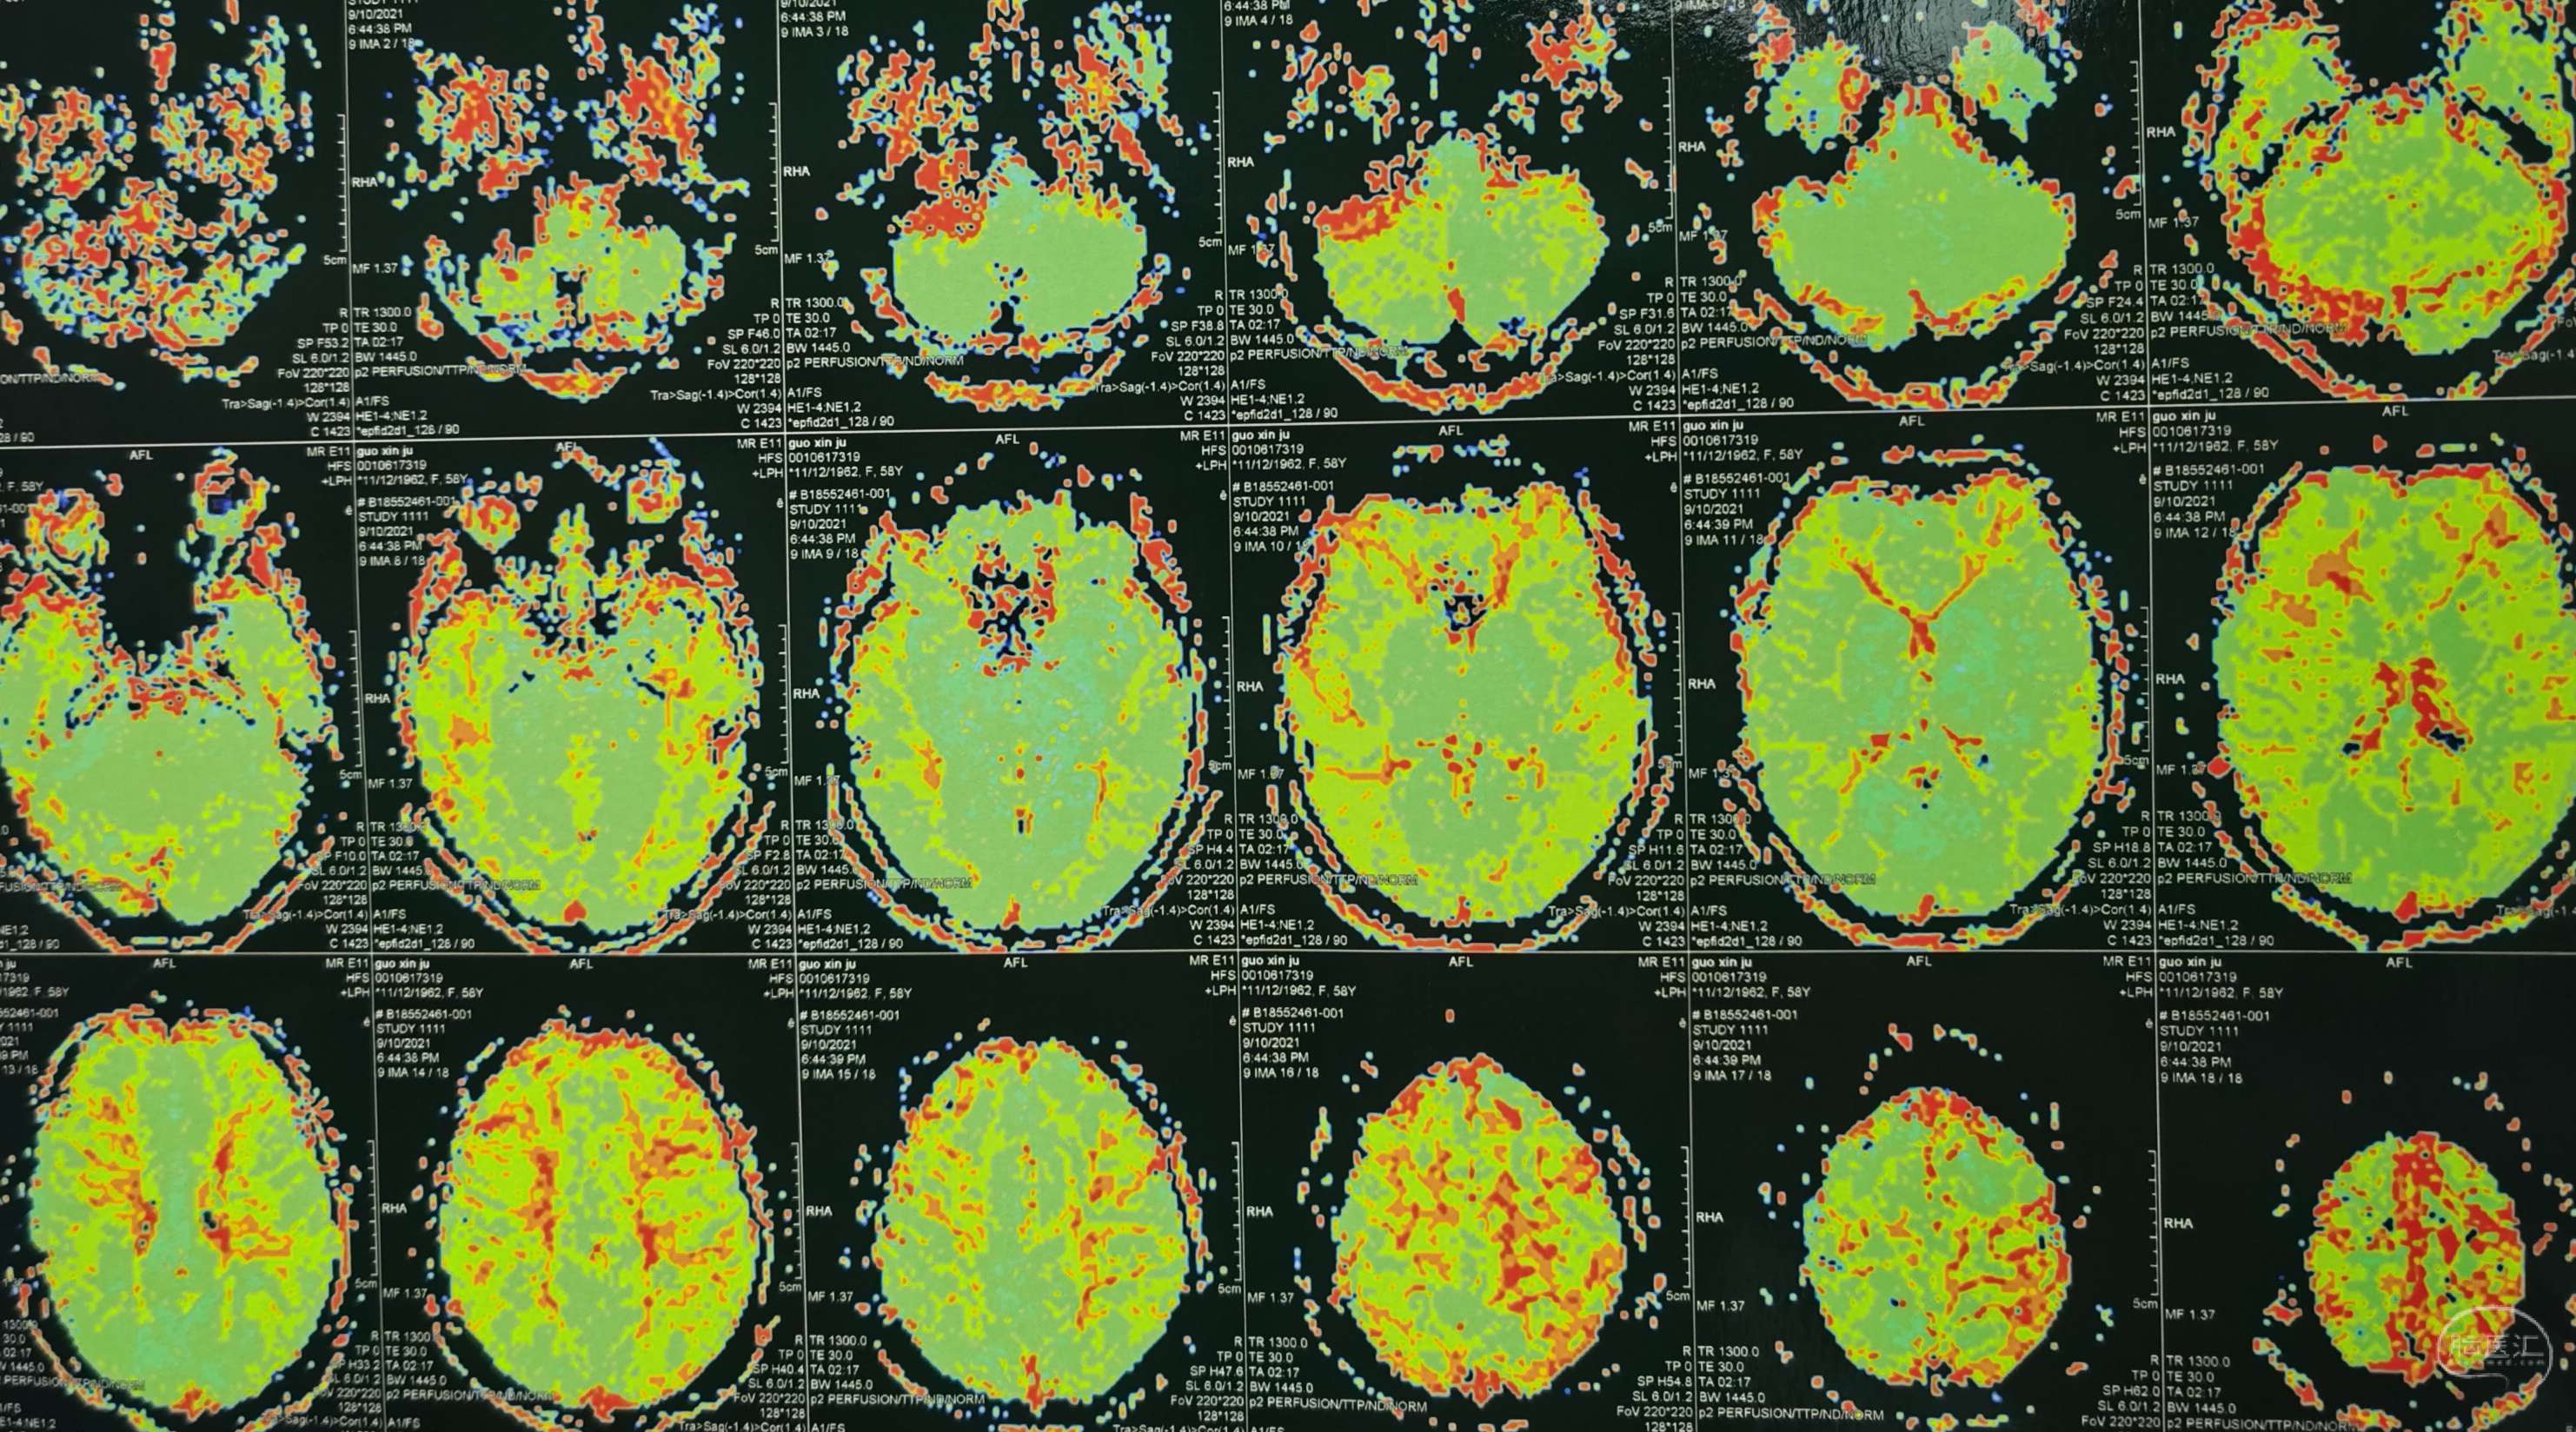

磁共振灌注提示:双侧大脑半球低灌注改变。